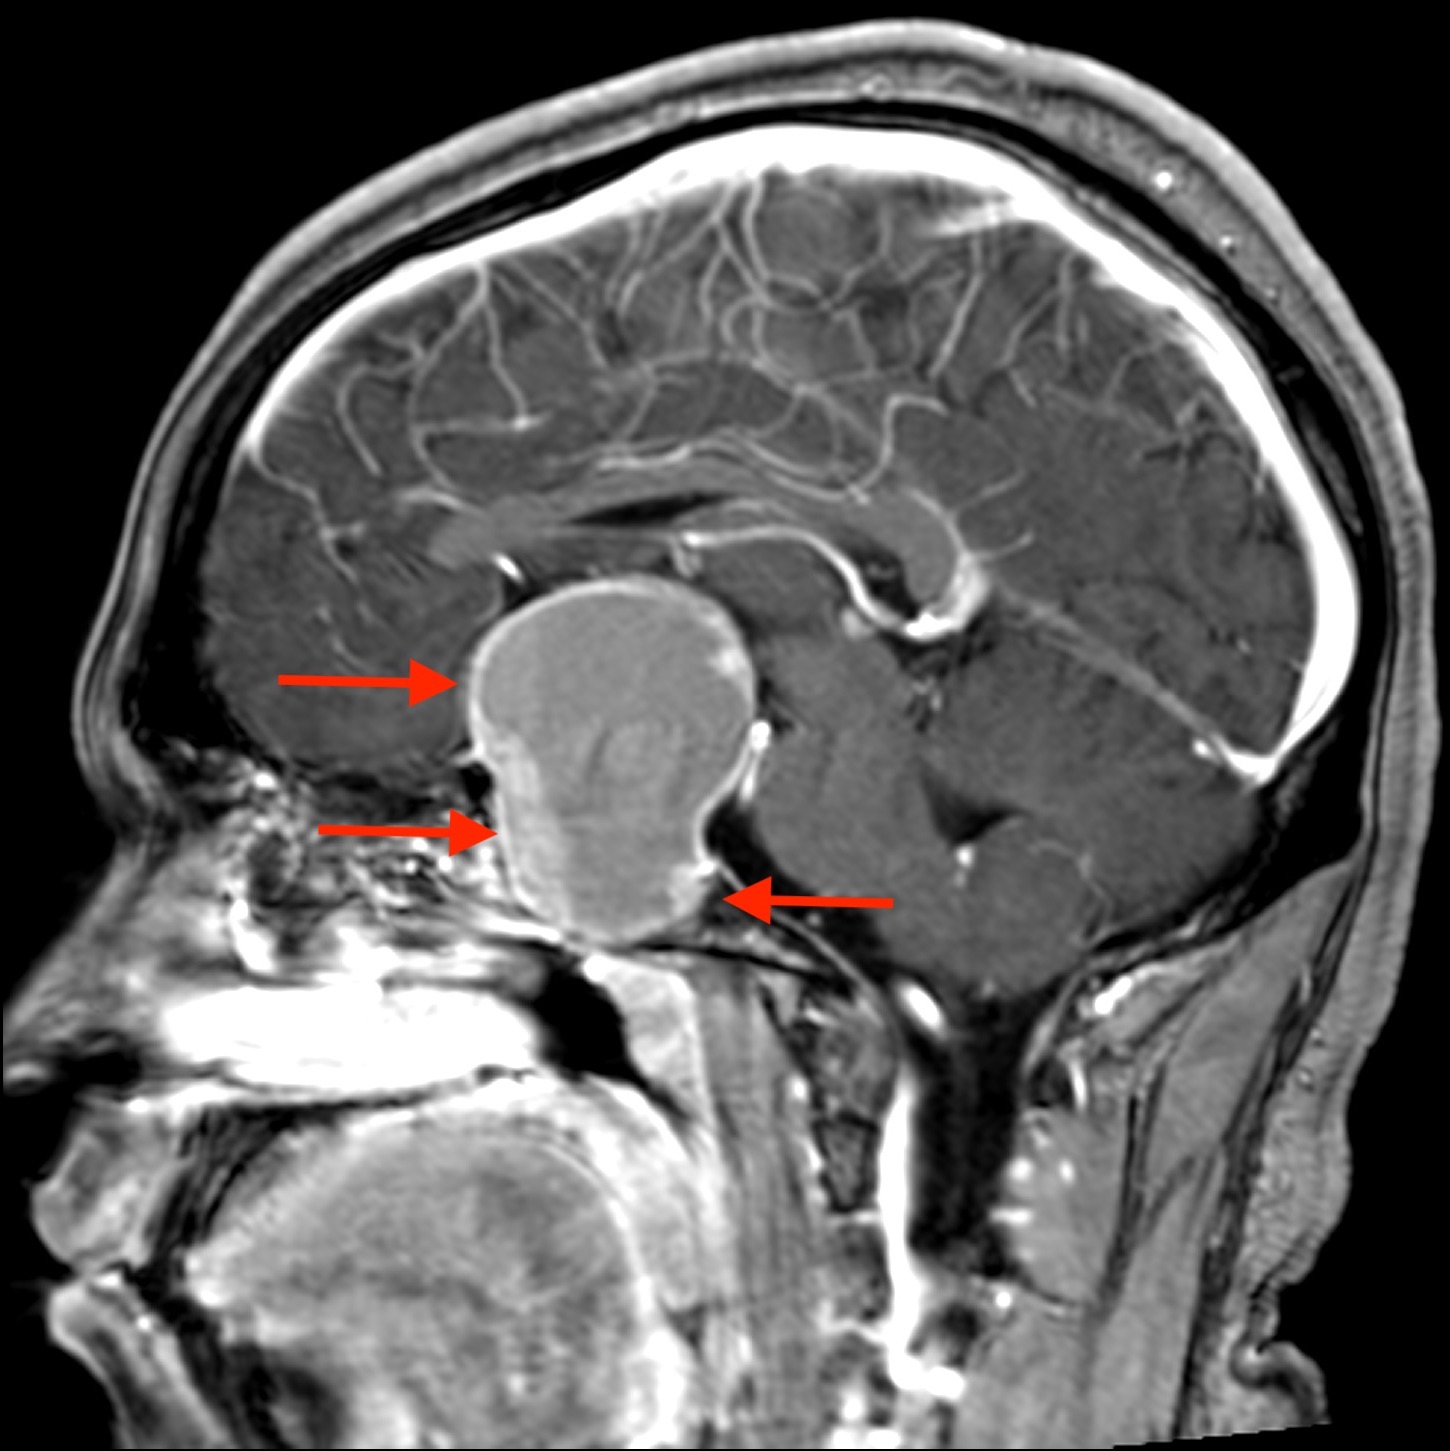

MRI results revealed a 5.5-cm solid and cystic mass with multiple fluid levels in the sellar and suprasellar areas, displacing and compressing the optic nerves and optic chiasm (Figures 1-3).

Figure 2. Sagittal postcontrast T1-weighted image showing enhancement of the nodular solid component anteriorly. Arrows indicate loculations of fluid.